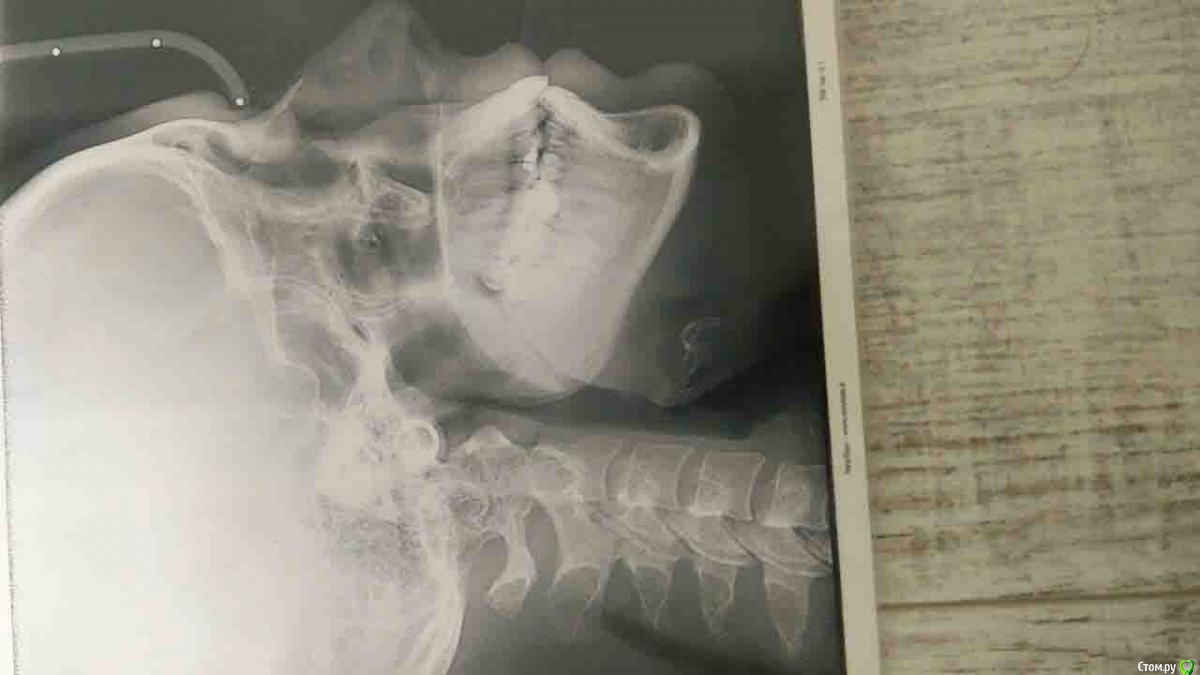

Валг Опубликовано 31 августа, 2018 Поделиться Опубликовано 31 августа, 2018 Добрый день!Нужен совет по поводу исправления прикуса, перекрестный, 3 класс, но точно я не уверена, врач мне мало что разъяснил. Ношу уже 4 месяца, и теперь врач мне говорит что нужно удалять нижние 5, так как они мешают смыканию челюстей и зубы вынуждены сильно наклонятся вперёд.Изначально ортодонт говорил, что удаление зубов не потребуется. Посоветуйте, пожалуйста, что делать! Ссылка на комментарий

Kazankov.Egor Опубликовано 1 сентября, 2018 Поделиться Опубликовано 1 сентября, 2018 Как минимум, я бы сейчас остановился: смущает то, что на ОПТГ (снимок всех зубов) центры зубных рядов более-менее совпадают, скорее всего это проблема зубных контактов, которые имеются на данный момент. Первое - депрограммирование челюсти. По остальному: нужно видеть фото полные внутриротовые и модели "до" и "на этапе". Ссылка на комментарий